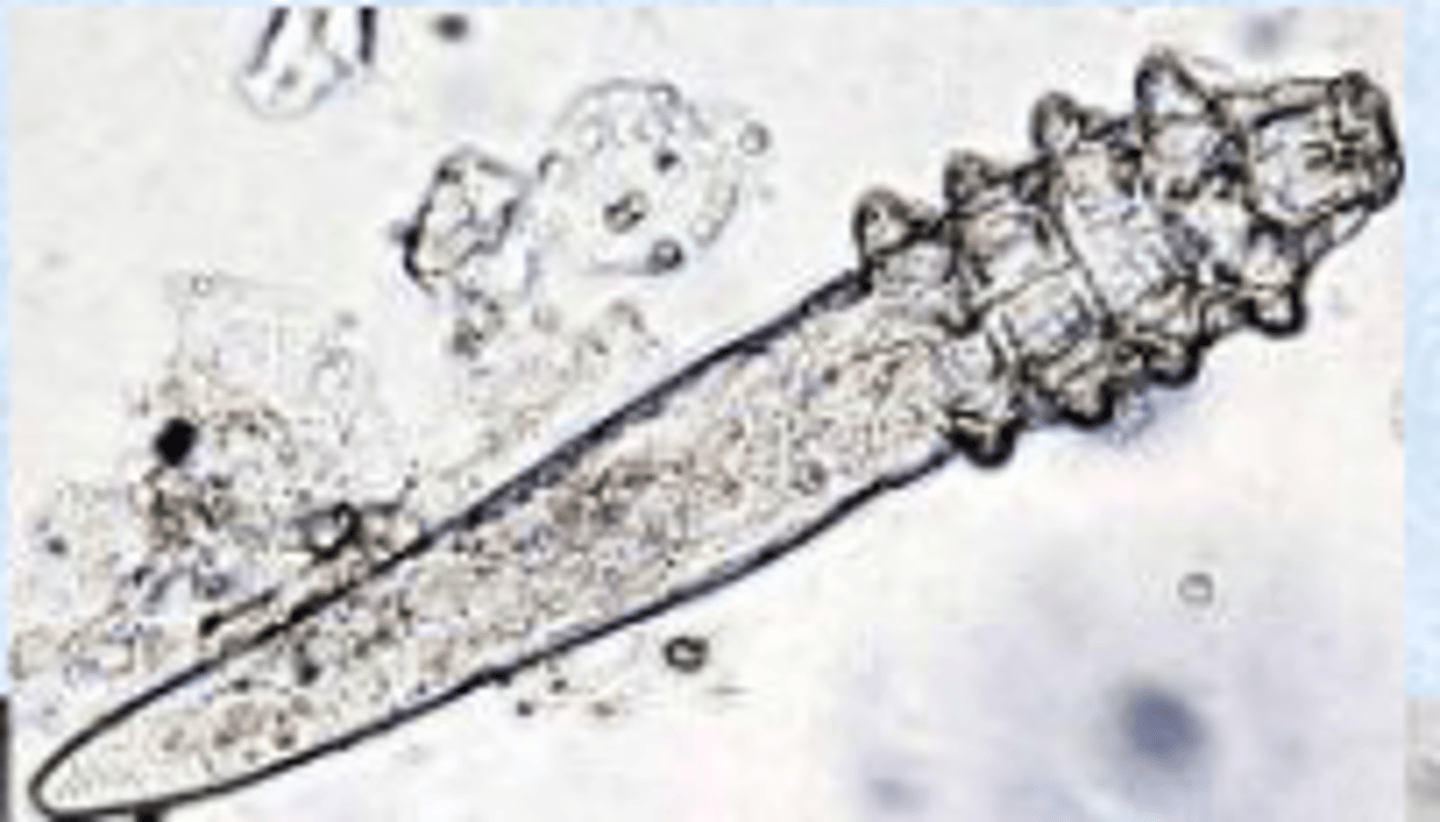

Demodex spp. common name

Red mange

Red mange info

Red mange look like